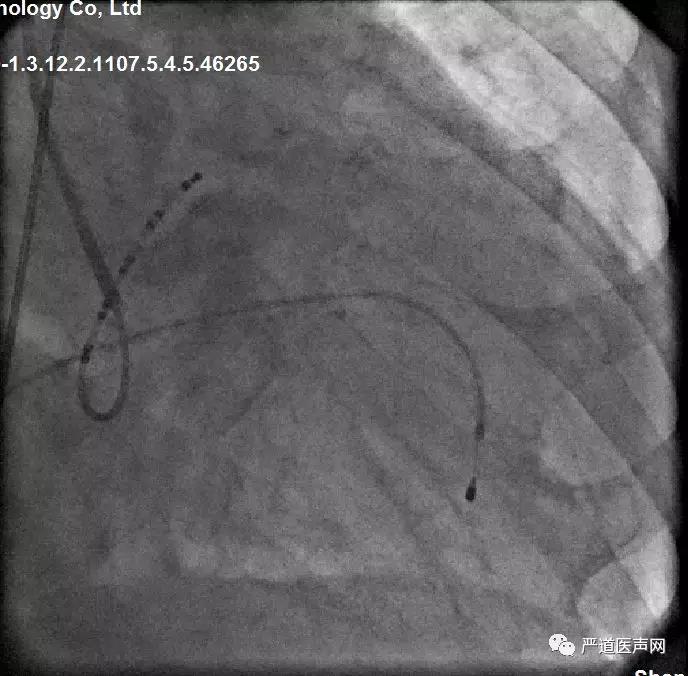

● LAO下用十级CS电极寻找冠状窦顺利,并将左室递送系统送入冠状窦内。

LAO